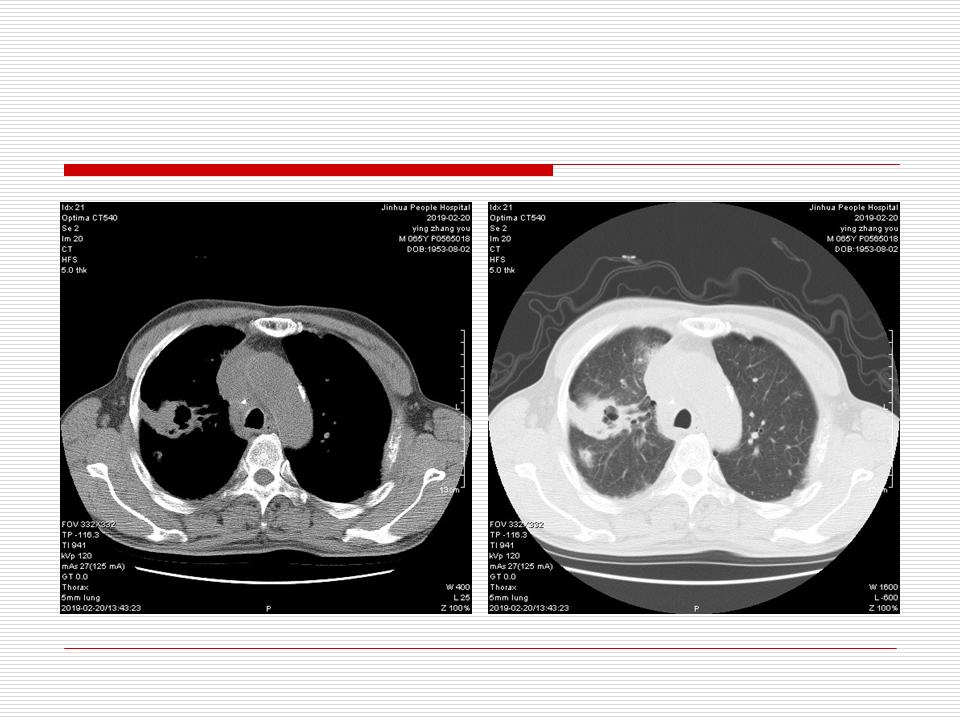

肺部阴影永恒且最重需要鉴别的是:到底是炎症还是肿瘤?但临床的病例中的影像表现难以界定或有些肿瘤特征,同时又有些炎症特点是非常常见的情况。作为临床医生我们怎么去总结分析,并找到之所以是炎症或之所以是肿瘤的细微差别或特点非常重要,也非常有用。2019.12.7浙江省2019年胸心外科学学术年会在宁波召开时,我的临床病例分析与经验总结<那些像肺癌的炎症与像炎症的肺癌>获得在大会交流的机会,以下为该PPT的内容,与你分享,希望对同道有益,有借鉴与启迪。若有探讨与进一不完善的建议,欢迎文末留言讨论: